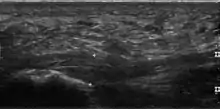

Thickened plantar fascia in ultrasound

The plantar fascia has three fascicles-the central fascicle being the thickest at 4 mm, the lateral fascicle at 2 mm, and the medial less than a millimeter thick.[19] In theory, plantar fasciitis becomes more likely as the plantar fascia's thickness at the calcaneal insertion increases. A thickness of more than 4.5 mm ultrasound and 4 mm on MRI are useful for diagnosis.[20] Other imaging findings, such as thickening of the plantar aponeurosis, are nonspecific and have limited usefulness in diagnosing plantar fasciitis.[13]